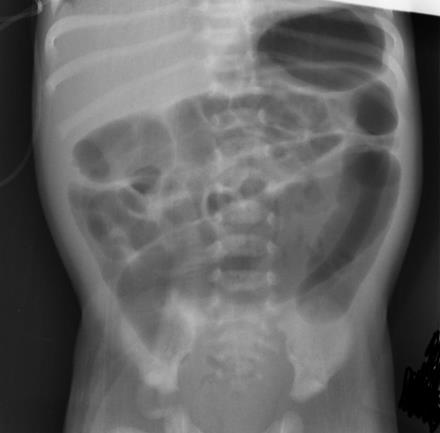

A plain abdominal x-ray may show non-specific signs of distal obstruction such as dilated intestines and air-fluid levels. There may be an absence of air in the lower pelvis. However, a normal film does not exclude the possibility of Hirschsprung's disease.

[Figure caption and citation for the preceding image starts]: Abdominal x-ray image showing gaseous distension of the large bowel with air absent from the rectum (typical of Hirschsprung’s disease)BMJ Case Reports 2012; doi:10.1136/bmj.e5521 [Citation ends].